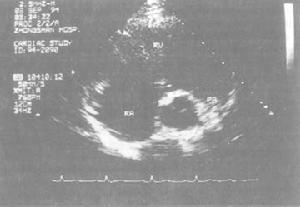

2、風濕性心臟病 肺心病患者在三尖瓣區可聞及吹風樣收縮期雜音,有時可傳到心尖部;有時出現肺動脈瓣關閉不全的吹風樣舒張期雜音:加上右心肥大、肺動脈高壓等表現,易與風濕性心瓣膜病相混淆。一般通過詳細詢問有關慢性肺、胸疾患的病史、有肺氣腫和右心室肥大的體徵,結合X線、心電圖、心向量圖、超聲心動圖等表現,動脈血氧飽和度顯著降低,二氧化碳分壓高於正常等,可資鑑別。